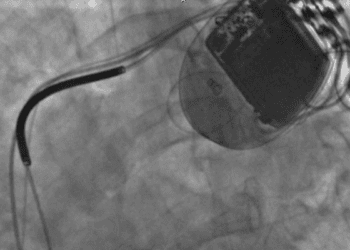

The Scan by 2 Minute Medicine®: Patient Zero: Immunotherapy for Brain Tumors?, Over-the-Counter Birth Control, Florida Supreme Court Deals a Devastating Blow to Abortion Access, Schwarzenegger’s Post-Pacemaker Update on Instagram